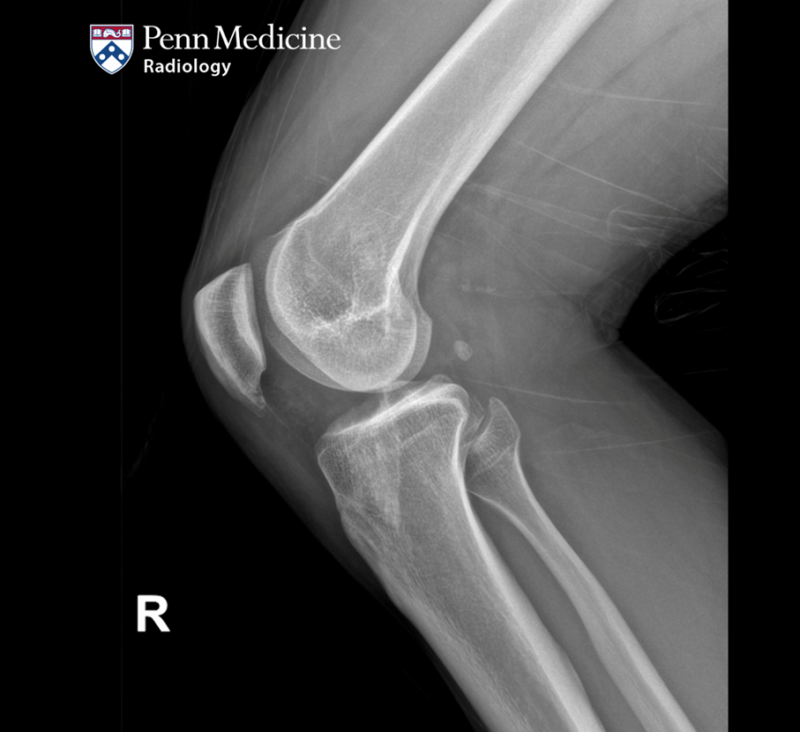

35-year-old woman with progressive pain and swelling in left lower leg

A 35-year-old woman presented to the emergency department with a three-week history of progressive pain and swelling in her left lower leg.